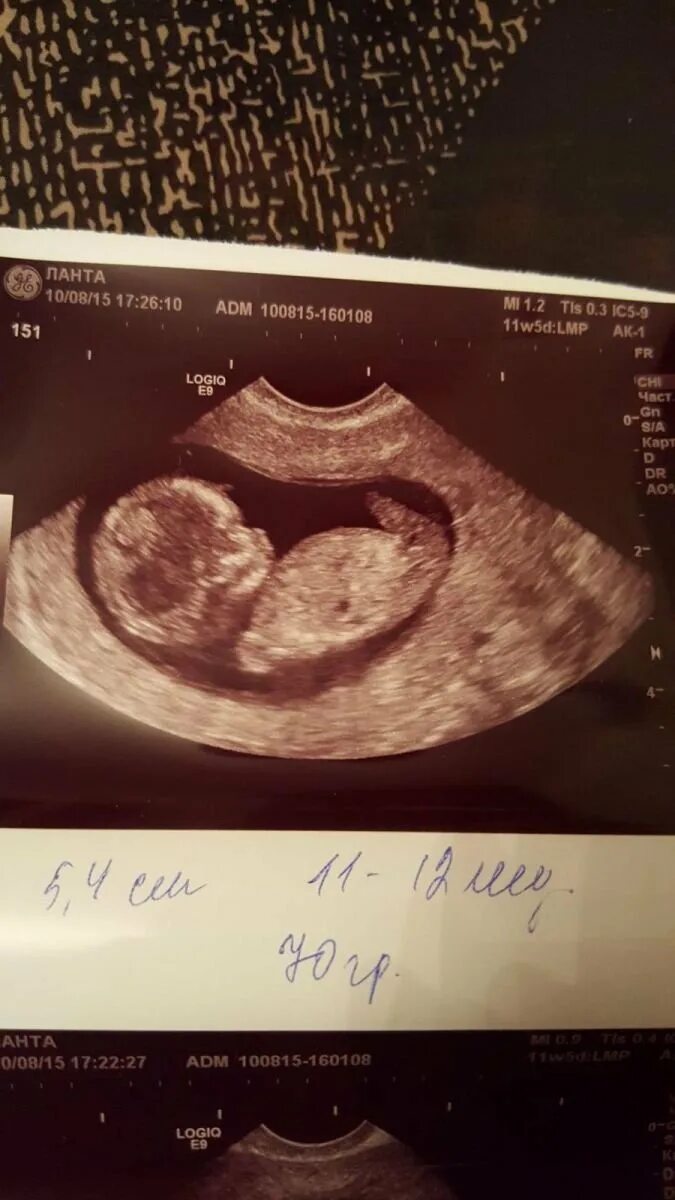

11 недель и 5 дней